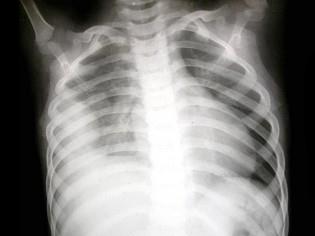

问题 男,5岁。发热、胸痛、胸闷、气促。X线检查如图,最可能的诊断为?(?)

选项 A.右侧胸膜间皮瘤 B.右侧肺脓肿 C.右侧包裹性积液 D.右侧肺不张 E.右侧气胸

答案 C